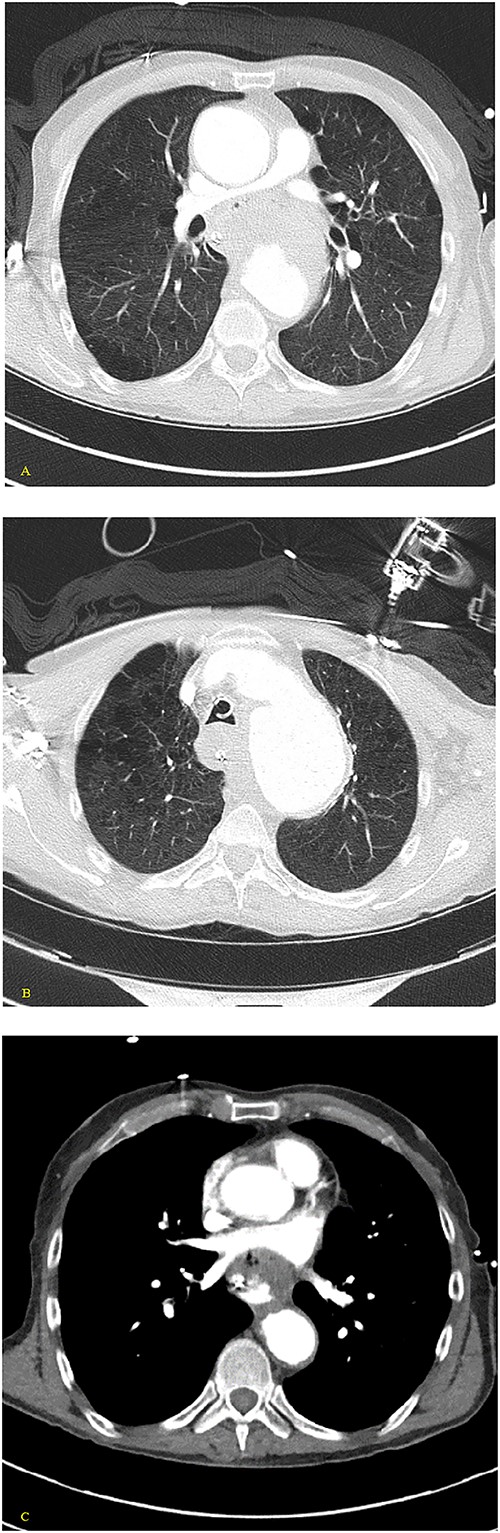

A 59-year-old male with no known previous medical history presented to a Level 1 trauma center after being discovered by EMS in a large volume of red blood. The event was unwitnessed by bystanders, so it was assumed that the mechanism was a traumatic fall with a resulting head bleed. During transportation patient lost pulses but returned to spontaneous circulation after cardiopulmonary resuscitation. The patient’s initial vital signs in the trauma bay were a blood pressure of 129/40 mmHg, a heart rate of 101 beats/min, and a Glasgow Coma Score of 3. The head was bandaged by EMS with red blood sticking to the patient’s hair, ears, and face. Upon unwrapping of the patient’s bandaged head, there was no source of bleeding nor was any trauma identified to the body. The patient was intubated and an orogastric tube was inserted with immediate drainage of 2L of bright red blood. The initial differential diagnosis was trauma in origin, including a basilar skull fracture with ingestion of blood or blunt abdominal trauma. Sonography identified no signs of internal peritoneal bleeding. Chest X-ray revealed large dilation of the thoracic aorta (Fig. 1). CT of the chest with IV contrast showed aneurysmal dilation of the ascending and descending thoracic aorta with max diameter of 65 mm, AEF at the level of pulmonary artery bifurcation and contrast extravasation into the esophagus and stomach (Figs 2–4). Octreotide was given and a massive transfusion protocol (MTP) was initiated with transfusion including 2 units of whole blood and 15 units of RBCs. Cardiothoracic surgery and interventional radiology were called to evaluate the patient; however, massive blood loss ultimately led to a myocardial infarction and the patient expired 75 min after admission.

(A, B) Axial nonenhanced CT chest with contrast and (C) axial enhanced CT chest with contrast reveal an extensive clot around the aorta and around the esophagus with some mass effect on the pulmonary arteries and the LA. Clot fills the aorta.